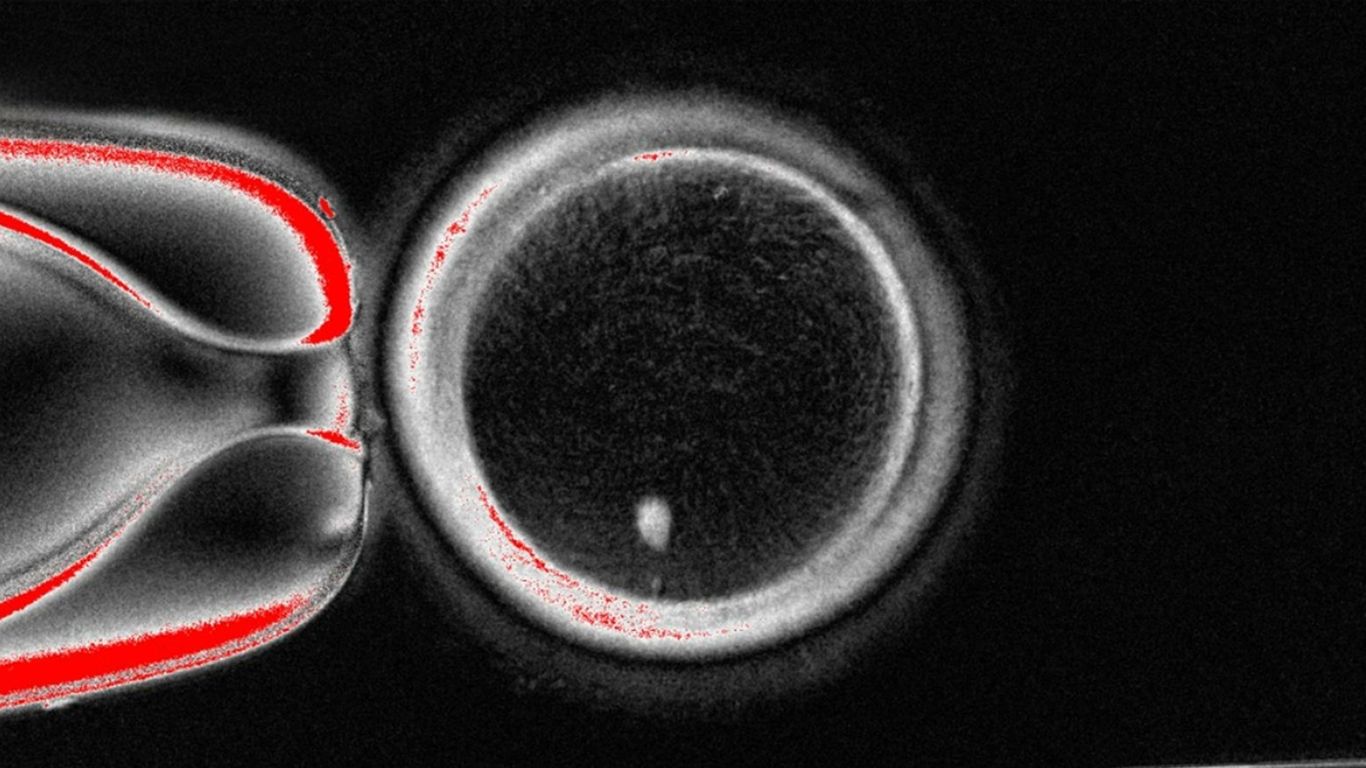

Scientists have used DNA from human skin cells to create "functional" eggs that can produce early human embryos, but more research is needed before these eggs can be used practically. The study represents early-stage research and highlights the potential for helping with infertility issues. The researchers note several limitations, including that the eggs currently develop abnormally and are not yet viable for creating pregnancies.

• Scientists turned DNA from skin cells into eggs that can make early human embryos.

• The eggs had chromosomal issues, and only a small percentage developed properly.

• The process involves combining cloning and fertilization by placing skin cell DNA into an egg.